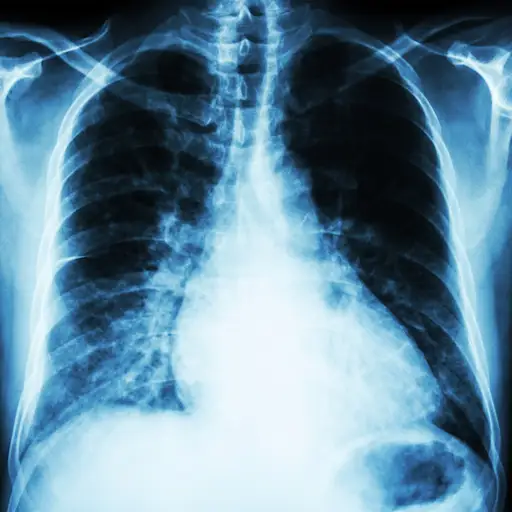

您的血液将进行钠的测试(低水平表明血液中的水过多),钾(低水平与中风,高血压和心脏病有关)以及其他可能表明心脏损伤的生物标志物。Contreras博士说,胸部X射线射线可以揭示您的肺部是否有液体或心脏肿大(表明您的心脏肌肉正在加班以抽血的迹象)。根据这些结果,您的医生可能会订购其他测试,包括运动应力测试,心电图,超声心动图和/或MRI。